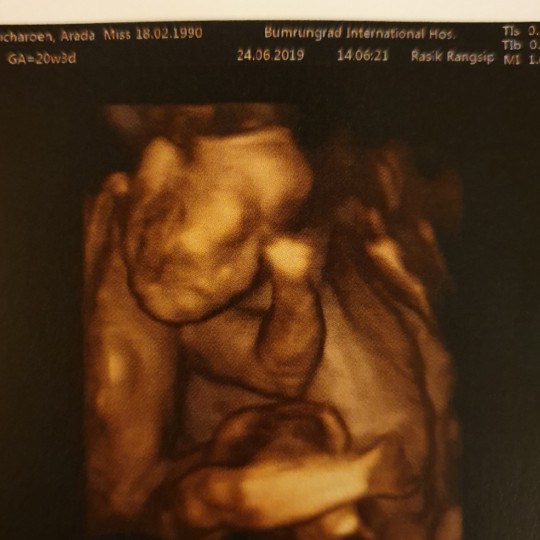

คุณแม่ท่านไหนคลอดเดือนพย.62มั้งค่ะขอเสียงหน่อย ได้ลูกสาวหรือลูกชายกันค่ะ ? บ้านนี้วันนี้พึ่งไปอัลตร้าซาวมาเป็นลูกสาวกำหนดคลอด21พย.ค่ะเห็นจิมิชัดมาก